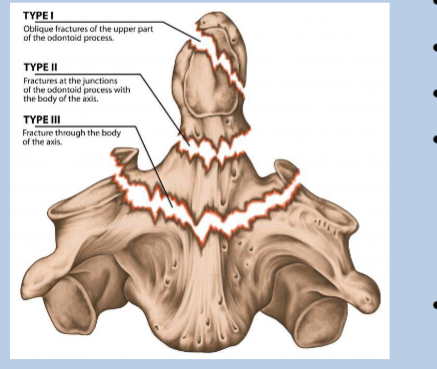

What does type 1 of odontoid peg fracture look like?

superior to the base

What does type 2 of odontoid peg fracture look like?

Transverse through the base

What does type 3 of odontoid peg fracture look like?

below base into the body